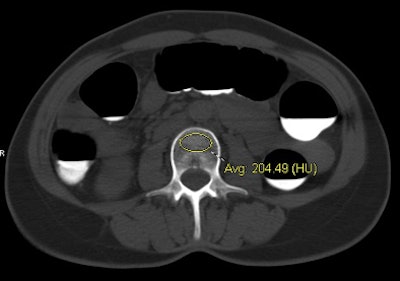

| CT data from virtual colonoscopy exam shows individual with normal BMD (top) and another with osteoporosis (bottom). Both cases were assessed at the L3 level using the simple ROI method, with results confirmed by DEXA. Images courtesy of Perry Pickhardt, MD. |

"We simply lay an ovoid ROI and measure the mean attenuation in Hounsfield units," he said. Reconstructions were performed at both 1.5-mm and 5-mm thicknesses and the two were compared -- but the focus was on 5-mm thicknesses because they are compatible with any routine CT study.

For example, at the L3 level, a trabecular attenuation threshold of 130 HU was 100% sensitive for osteoporosis (29/29); 61 (72.6%) of 84 adults with normal BMD were above the 130 HU threshold, while 108 (82.4%) of 131 below 130 HU had osteopenia or osteoporosis at DEXA. Similar results were found for other T12-L5 levels; complete results are shown below.